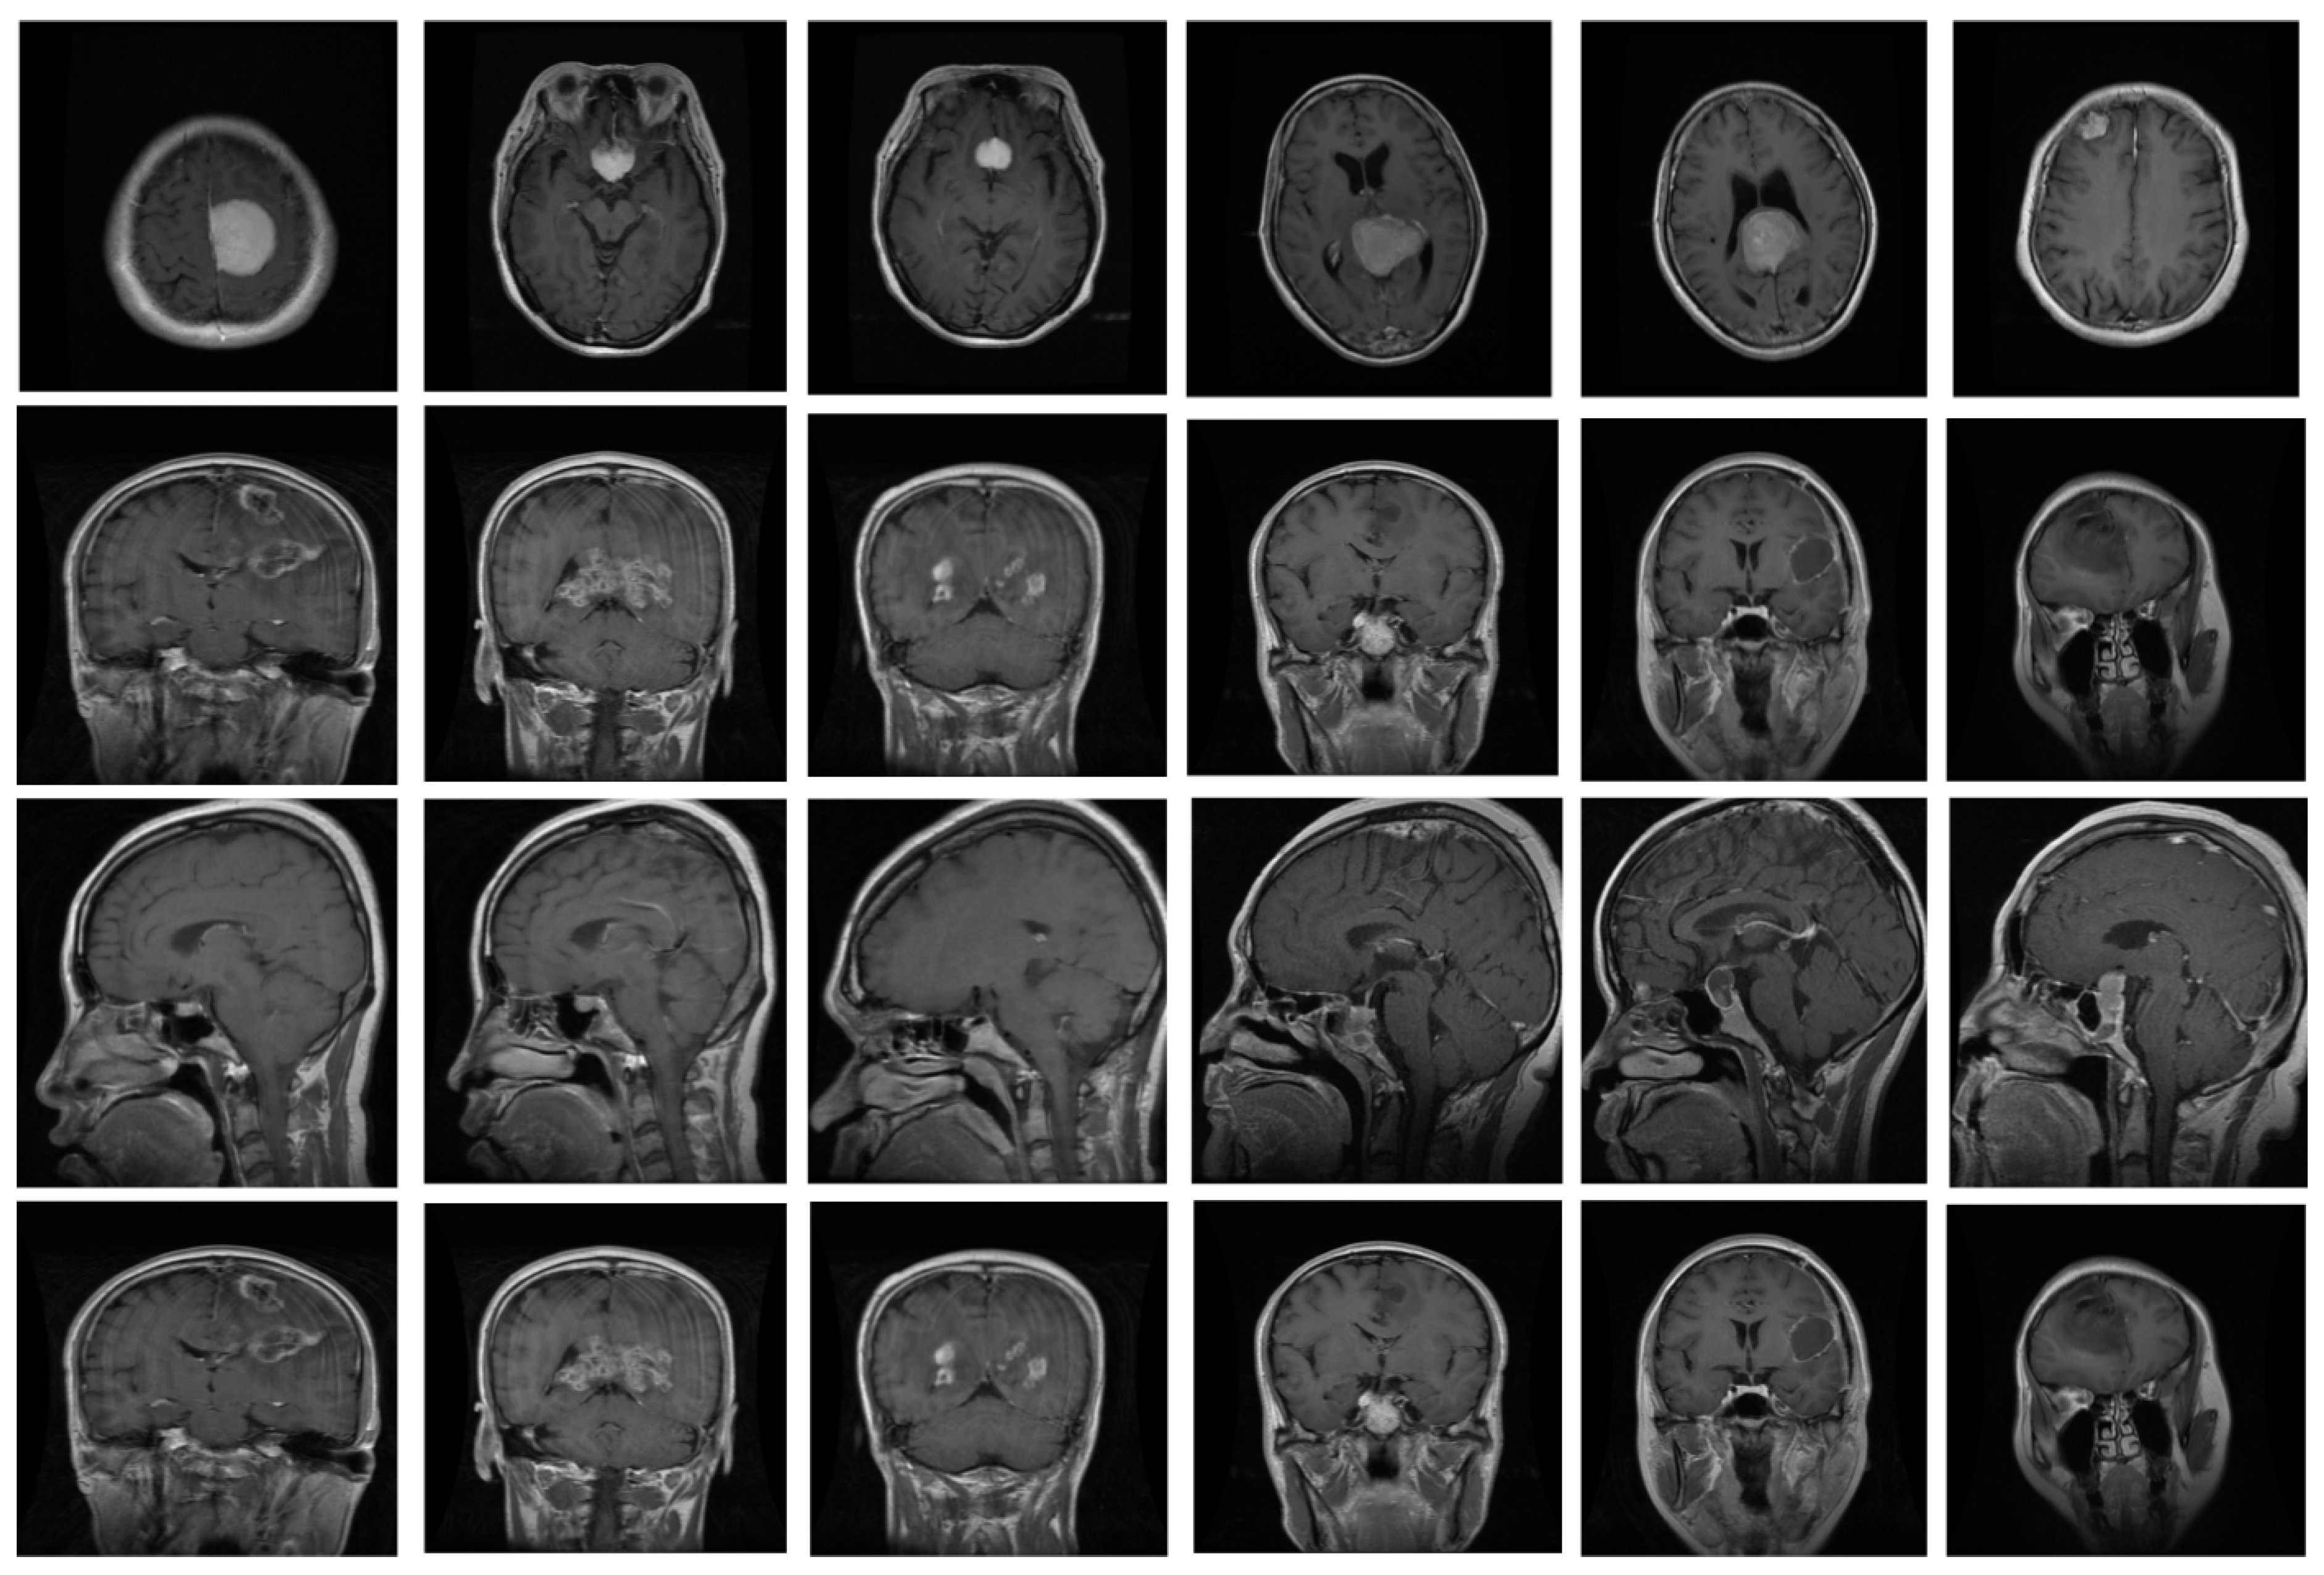

Figure 4. Some samples of brain MRI.

The proposed system underwent training and evaluation utilizing two distinct datasets: the Figshare dataset and Harvard medical images [31]. The Figshare dataset encompasses T1-weighted contrast-enhanced MRI images sourced from 233 individuals, yielding a total of 3064 brain images. This dataset consists of three categories of brain tumors, namely pituitary (930), glioma (1426), and meningioma (708), all of which were obtained from Nanfang hospital in China. The samples in this dataset measure 512 × 512 in size. On the other hand, the Harvard medical dataset was composed of ten tumors, as diagnosed by various experts. The brain MRIs in the Harvard dataset were captured in the axial plane, T2-weighted, and measured 256 × 256 pixels. We assessed the efficacy of our proposed detector using both datasets, but we only utilized the Figshare dataset for training purposes. Some sample images are depicted in Figure 4.